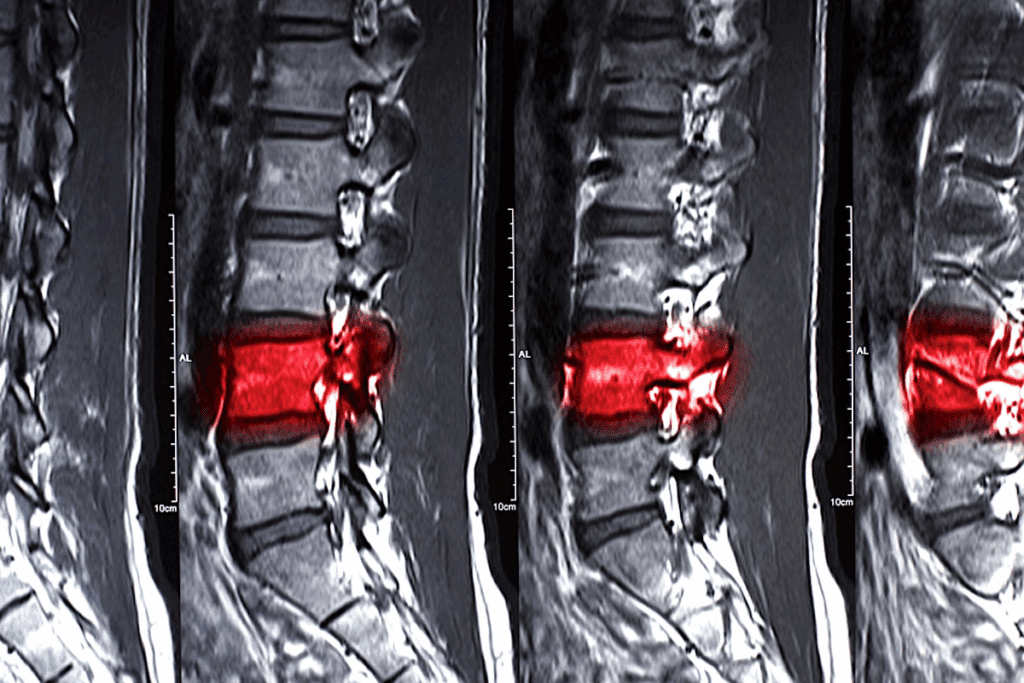

Diagnostic Approaches

Diagnosing L5 S1 conditions involves physical exams, patient history, and imaging. MRI scans are very helpful. They show detailed images of soft tissues like discs and nerves.

Healthcare providers check muscle strength and pain during physical exams. This helps find the problem’s source. Knowing this is key for creating a good treatment plan, whether it’s l5 s1 disk protrusion treatment or other methods.